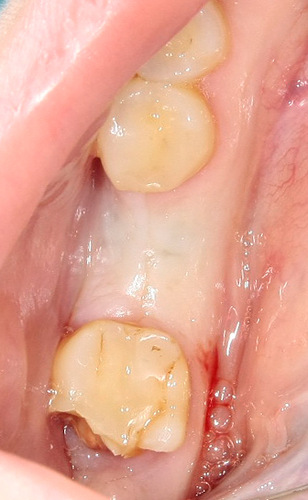

Ну ладно, удалили зуб. Что делать с лункой?

Правило третье — никаких выскабливаний, мы с вами не аборт делаем. Кюретаж необходим только в случае наличия явной гранулемы у корня зуба, либо если вы подозреваете, что по краям лунки (как правило, в пределах слизистой оболочки) остались мелкие кусочки зуба. Всё дело в том, что оставшиеся в лунке периодонтальные волокна — важный фактор удержания в ней кровяного сгустка. Если их выскоблить «до зеркального блеска», как написано в некоторых старых учебниках, то потом будем лечить альвеолит.

Правило четвертое — швы. В случае, если лунка зуба получилась большая, или для удаления зуба делались дополнительные разрезы — необходимо наложение швов. Идеальные материал для швов на лунки зубов — Vicryl или PGA, размером 3-0 или 4-0. Если предполагается одеть съемный протез зуба сразу после удаления, то можно использовать более тонкий шовный материал.

Наглухо ушиваются лунки только ретинированных зубов. Если коронковая часть зуба видна хотя бы частично, герметичные швы могут привести к осложениям: инфицированию области лунки и развитию абсцесса.